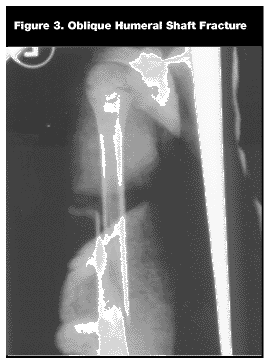

Humerus: Shaft. Shaft fractures of the humerus are not common. When they do occur, the middle third is the most common location.4,5 Falling on an elbow or hand can cause an oblique or comminuted fracture. Spiral fractures may occur if the body twists during the fall. Although these fractures may occur from accidental trauma, they should raise concern about potential non-accidental trauma, as a twisting force is necessary for this type of fracture.4,5,14

The child usually will have pain with motion on examination. Swelling, tenderness, and sometimes deformity can be seen. The radial nerve may be injured, and it is important to check for sensation dorsally between the thumb and index finger. Motor function can be checked by having the patient extend the wrist and finger extensors. AP and lateral radiographs are sufficient for the diagnosis. (See Figure 3.)